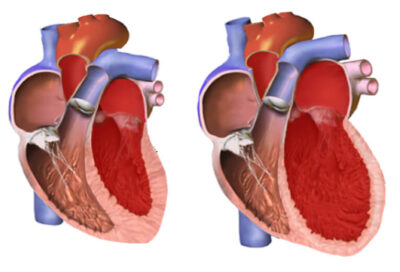

El músculo cardíaco funciona como una bomba que debe impulsar la sangre en contra de una presión máxima para la cual fue diseñado. Una presión mayor supone una carga extra, lo cual hace que las paredes del ventrículo izquierdo se engrosen anormalmente y, en fases más avanzadas debido al sobre-uso, se estire y pierda su capacidad de bomba.

Estos fenómenos son conocidos medicamente como HVI: hipertrofia ventricular izquierda e, ICC: Insuficiencia cardíaca congestiva. La expresión sintomática de esta falla es dada por la acumulación del “volumen plasmático” (la sangre contenida en nuestras venas) o “precarga”.

Este volumen excesivo en el sistema vascular, genera “edema” (hinchazón en las piernas que puede avanzar hasta “ascitis” (retención de líquido en la cavidad abdominal y hasta en los pulmones causando dificultad respiratoria y un estado general de salud muy deteriorado.